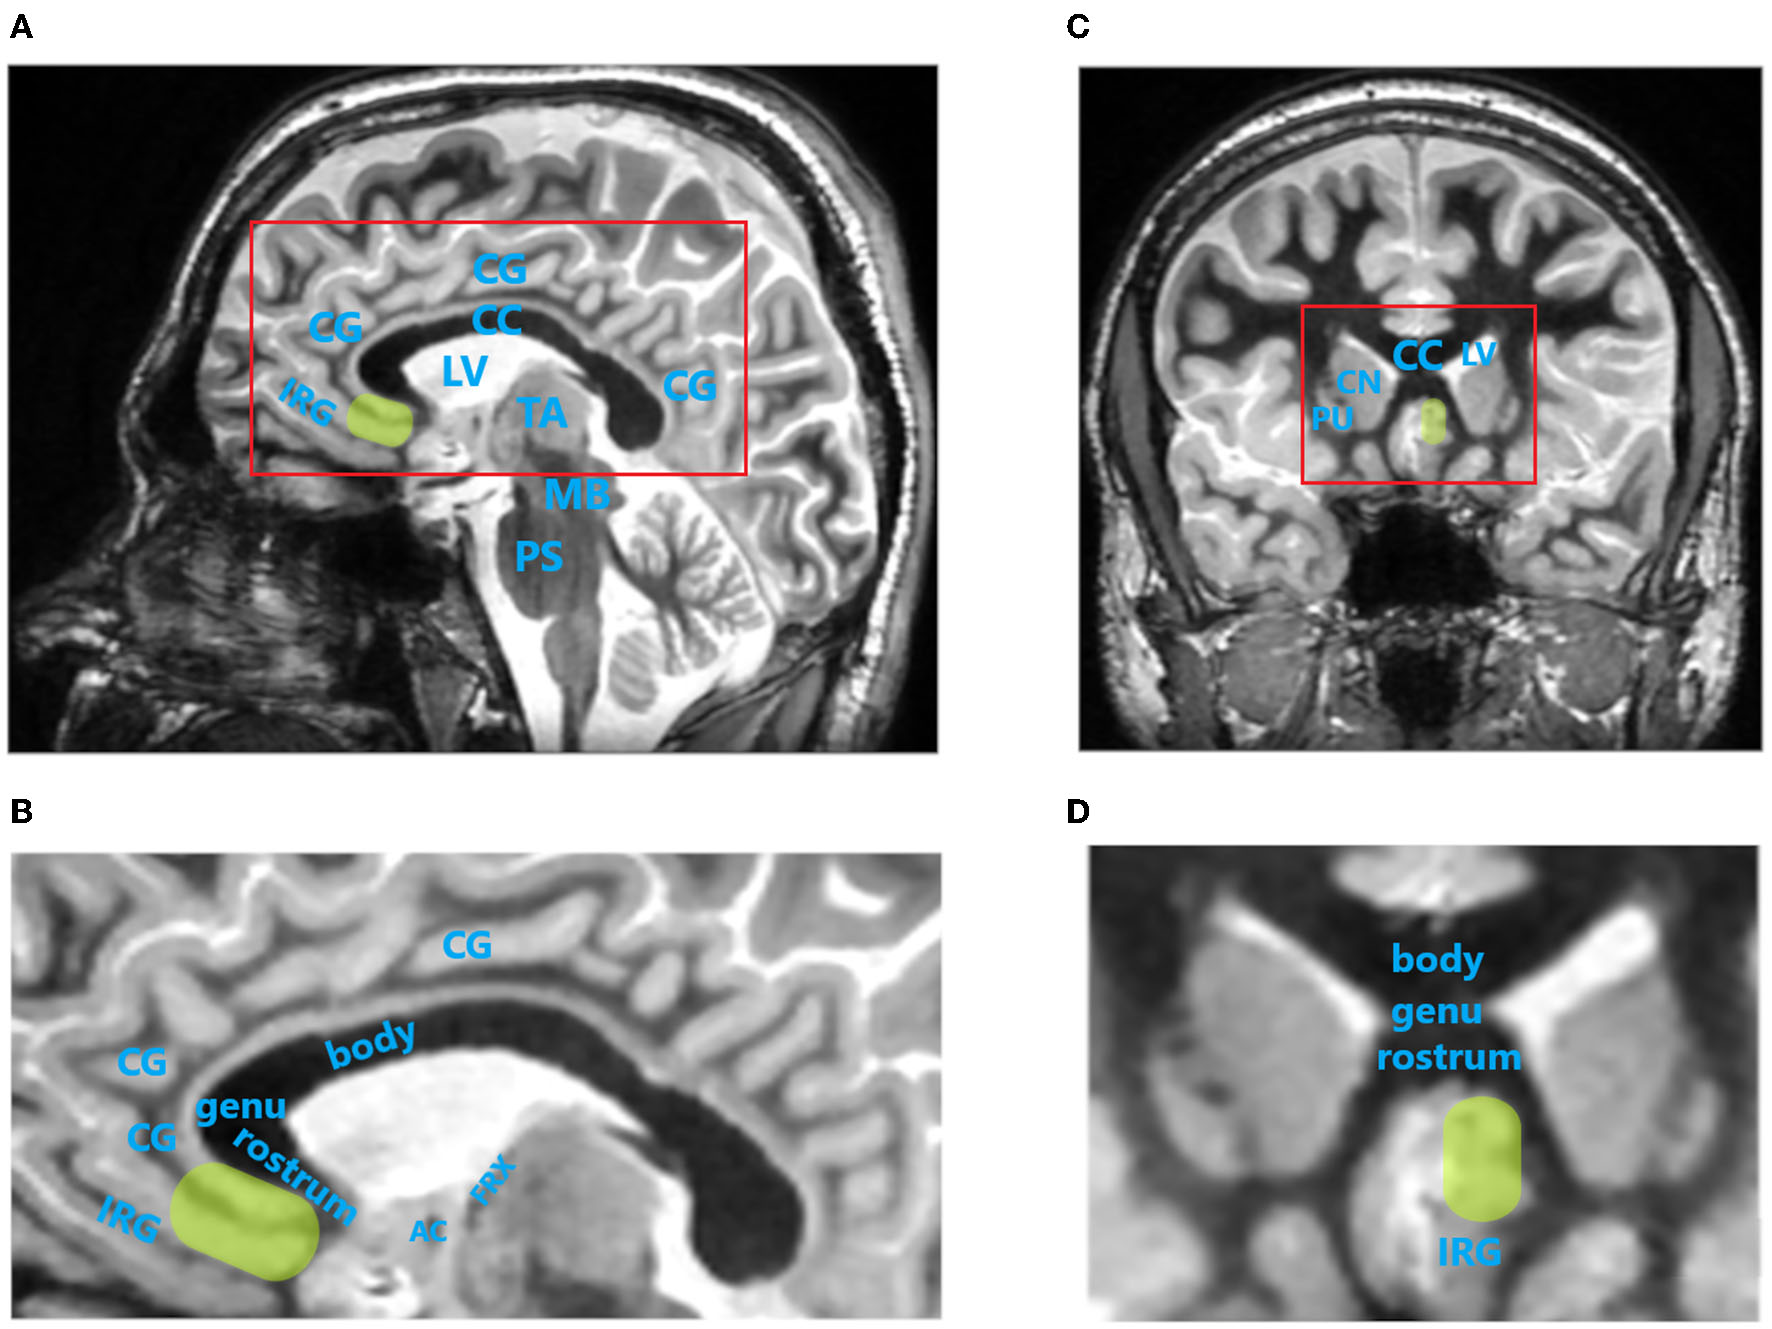

The primary aim of SCC DBS for TRD is to reduce activity within this brain region while increasing the activity of dorsal limbic and neocortical regions, especially the dlPFC, dorsal anterior cingulate, posterior cingulate, and premotor and parietal regions, which correspond with clinical improvement in patients with MDD (11, 16, 17). Localization of the SCC by MRI using a Fast Gray Matter Acquisition T1 Inversion Recovery (FGATIR) sequence is shown in Figure 2. The SCC has been marked in yellow color to surrounding brain structures.

Figure 2. Localization of the subcallosal cingulate cortex (SCC) by magnetic resonance imaging (MRI) using Fast Gray Matter Acquisition T1 Inversion Recovery (FGATIR) sequence. SCC is indicated by green oval region. (A), Paracentral image of sagittal brain MRI scan. Red rectangle indicates brain region magnified in (B). (B), Magnified sagittal MR image of cingulate cortex region. (C), Image of coronal brain MRI scan at the level of SCC. (D), Magnified coronal MR image of cingulate cortex region. AC, anterior commissure; body, body of corpus callosum; CC, corpus callosum; CG, cingulate gyrus; CN, caudate nucleus head; genu, genu of corpus callosum; FRX, ascending column of fornix; IRG, inferior rostral gyrus; LV, lateral ventricle; MB, midbrain; PS, pons; PU, putamen; rostrum, rostrum of corpus callosum; TA, thalamus. MRI images were acquired on 3T SIGNA Architect scanner (GE Healthcare).